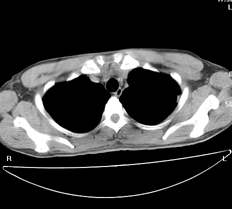

左肺上叶尖后段胸膜下可见两个类圆形薄壁空洞,内外壁较光滑,腔内为气体密度,支持结核性薄壁空洞。

左飞上叶尖后段两个含气的囊性肿块,边界清晰,其周围未见卫星病灶,考虑肺囊肿.不支持肺结核是因为未见卫星灶,临床未见体征.

左肺上叶后段见两个孤立圆形厚壁空洞,无液平及壁结节。周围清晰,无卫星灶。结合病史,如此大的病灶病人毫无感觉,另外周围如此清晰,应能排除结核空洞;肺囊肿壁应更薄,如合并感染可增厚,但周围应模糊。本人考虑:肺韦格肉芽肿。

左上叶尖后段可见两个中等壁厚空洞,腔内无液平,内外壁光整,局部轻度胸膜增厚,首虑结核。

考虑肺囊肿可能性大。不支持结核是因为周围肺野内未见明显卫星灶及纤维索条,不支持韦格氏肉芽肿是因为内壁及外壁均很光整,壁厚薄一致,而韦格氏肉芽肿洞壁厚薄多不均匀,内壁多不规则,其内可有形态不规则的内容物。

左肺尖后段的两个薄壁(纵隔窗)含气囊样病变,壁厚薄较均匀、光整、内无液气平形成、其邻近肺野见

少许渗出、未见卫星灶,其余肺野未见明显支气管播散灶(楼主虽然未上传全其他层面图片,但认为因正常而未上传)。

综合上述:考虑为肺囊肿合并感染,不支持结核空洞(虽然病变位于结核好发区,但认为这么明显的结核空洞应该有明显的肺内支气管播散灶)。